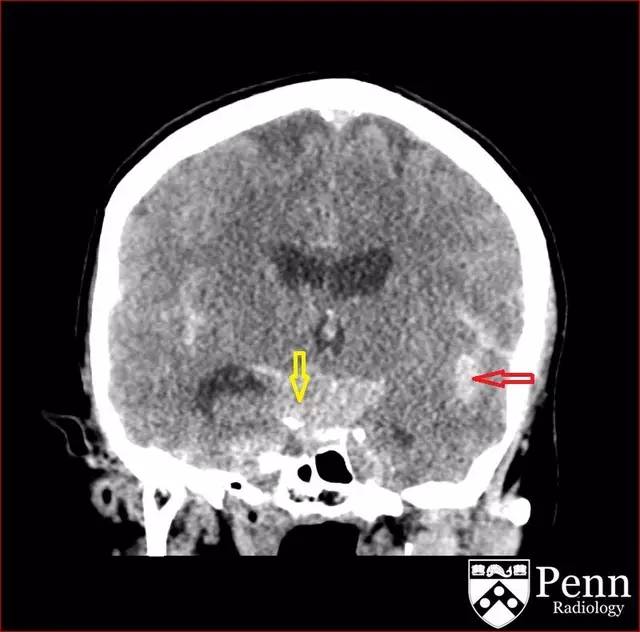

图 1 平扫 CT 可见广泛的蛛网膜下腔出血,累及基底池(黄色箭头)、外侧裂(红色箭头)

图 2 平扫 CT 可见广泛的蛛网膜下腔出血,累及基底池(黄色箭头)、外侧裂(红色箭头)

CT 可见广泛的蛛网膜下腔出血,累及基底池、外侧裂并延伸到额叶。